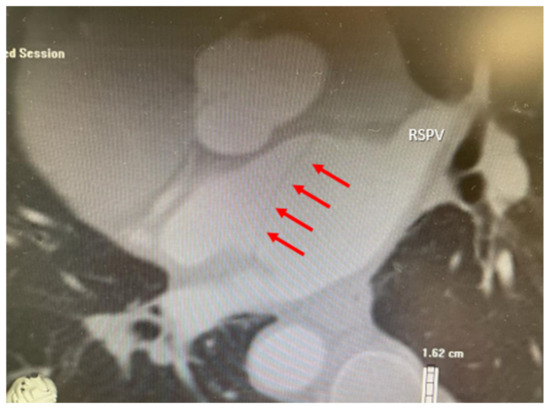

2. Case Presentation